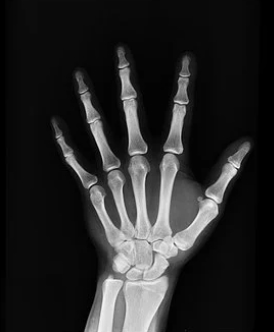

보통 성장판은 손목이 가장 빨리 닫힙니다. 일반적으로 성장판 닫히는 순서는 손목, 어깨, 팔꿈치, 무릎, 발목, 손가락, 발가락 뼈들입니다.

급성장기에는 성장판 검사를 통해 우리 아이 골연령의 속도가 빠른지, 느린지 급속도로 빨라지지는 않았는지 체크가 필요합니다.